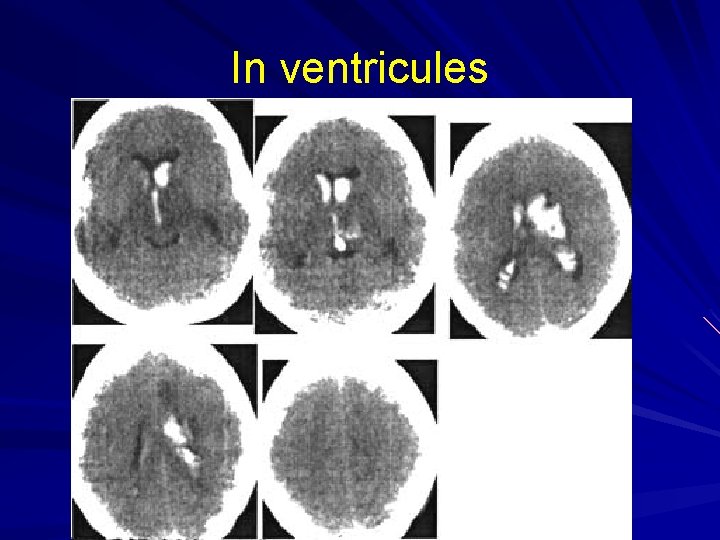

In ventricules

Complication of intracerebral hemorrhage is rupture into the ventricle system. This is usually associated with: worsening of patient’s state Hyperthermia breathing disorders hormetonia manifests as changes of muscle tone in extremities, when hypotonia is changed into hypertonia in a few seconds or minutes.